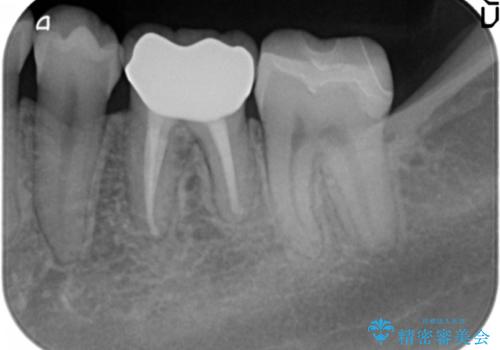

また、左下6番は専門医(銀座院院長 Dr.林)による再根管治療を行いました。

- 38万円(左下7:歯周外科処置5万円、セラミックインレー7万円 左下6:精密根管治療(再治療・専門医による)13万円、ファイバーコア2万円、ジルコニアクラウン10万円、仮歯1万円)費用は治療当時の料金となります